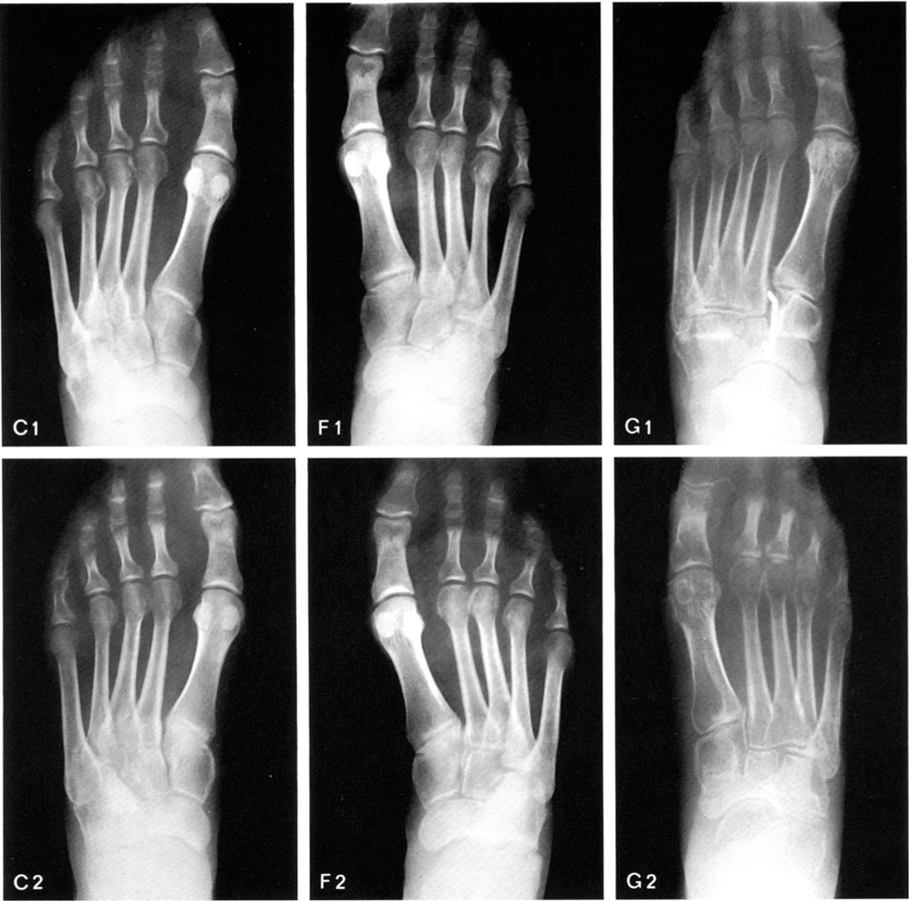

Pes Cavus L? G?. Symptoms predominantly include a high arch of the foot resulting in pain and possible fractures pes cavus is characterized by a high arch that places stress on both the ball of the foot and the heel of the foot. This deformity does not flatten on weight bearing.

Patients complain of a variety of symptoms depending on the degree of deformity. 2 the deformity can be located in the forefoot, the midfoot, the hindfoot, or a combination of these sites. In this study, the authors identified 310 cases of pes planus:

Treatment of cavus due to muscle imbalance. Common complaints associated with pes cavus include pain under the metatarsal heads and the heel, lateral ankle sprains, and footwear issues. The feet don't lie flat properly, with the effect of undue forces in the wrong places causing bone or tissue damage. Pes cavus is a multiplanar foot deformity characterised by an abnormally high medial longitudinal arch.